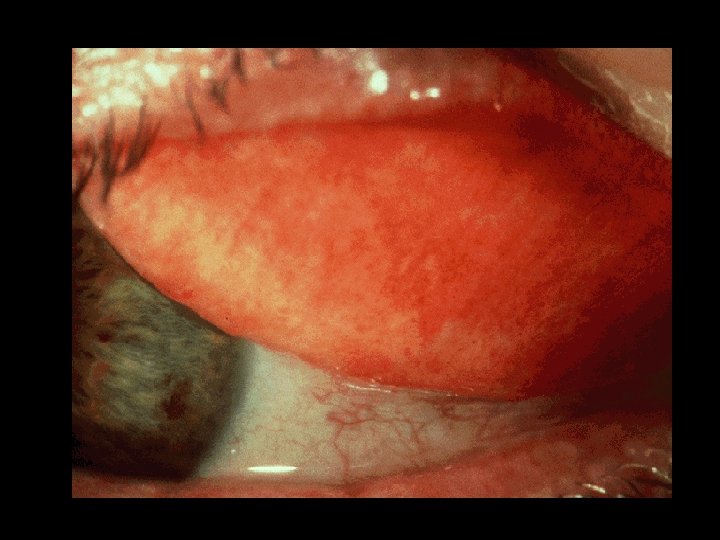

Acne Rosacea • “Rosy” dilatation of the central face: – eyes, nose, chin, cheek, forehead • Diverse spectrum of disease • pustules, nodules, cysts) Rhinophyma -hyperplasia of the nose in middle aged men (papules,

Acne Rosacea • Look for periodic facial flushing after • • temperature increase, spicy food ingestion or alcohol Absence of comedones Disease is chronic: Treatment goal is control

Acne Rosacea: Differential Diagnosis • Acne Vulgaris: • Seb. dermatitis: • Lupus: • Carcinoid: comedones, younger patient, lack of flushing, less erythema no acneiform lesions no papules and pustules flushing is transient